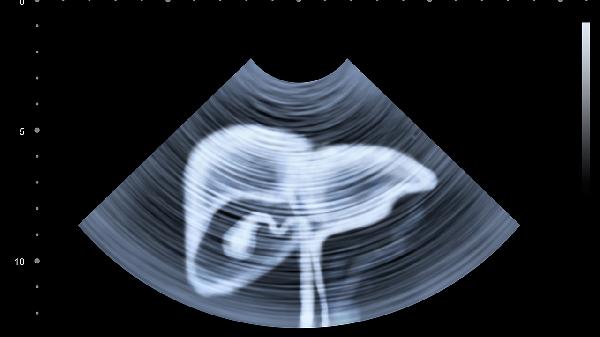

1、腹主动脉搏动是腹部跳动的最常见原因,尤其是在瘦弱或腹壁较薄的人群中更为明显。腹主动脉靠近腹壁,心脏搏动时血液流动产生的压力会被感知为跳动。这种情况通常无需治疗,但若跳动频率异常或伴随疼痛,需通过超声或CT检查排除腹主动脉瘤等病变。

5、若腹部跳动伴随其他症状,如持续性疼痛、发热、恶心或呕吐,需警惕腹部器官病变,如胃炎、胆囊炎或阑尾炎。此时应及时就医,通过血液检查、超声或内镜检查明确诊断,并根据病因进行药物治疗或手术干预。